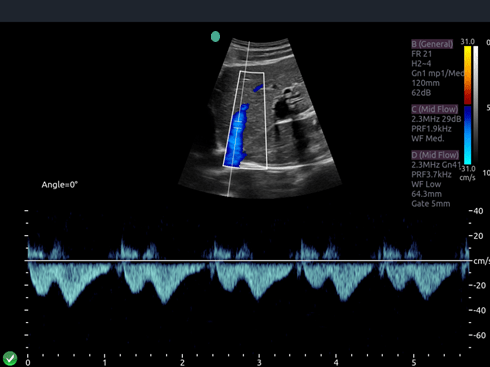

Invictus E5

O ultrassom Invictus E5 apresenta um design moderno e exclusivo, com perfeito fluxo de trabalho e interface intuitiva.

Dentre suas características inovadoras, podemos destacar a tela em LCD com rotação de 60° para ambos os lados, para otimização da visualização durante os exames; tela touch screen com menu totalmente customizável; painel de controle totalmente selado para facilitar limpeza e desinfecção da superfície, o que o torna referência para ser utilizado principalmente em Centro Cirúrgico.

Apresenta excelente qualidade de imagem, trabalho otimizado através de presets pré-determinados, sensibilidade e eficiência em aplicações de Point of Care e portanto, uma perfeita relação custo benefício.